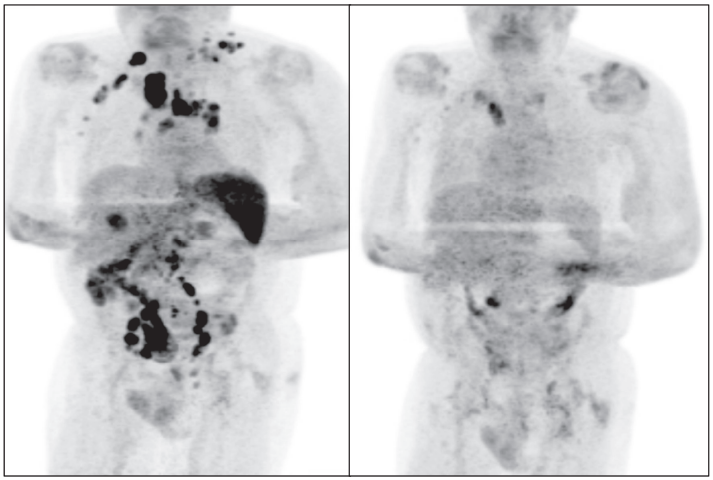

四個月后,患者身上可觸及的淋巴結(jié)腫大有所減輕少,臨時PET / CT掃描顯示淋巴結(jié)病的廣泛消退。EBV病毒PCR也降至413拷貝/ ml(log 10 2·62)。

左圖為最初的PET/CT掃描結(jié)果,右圖為4個月后的PET/CT掃描結(jié)果